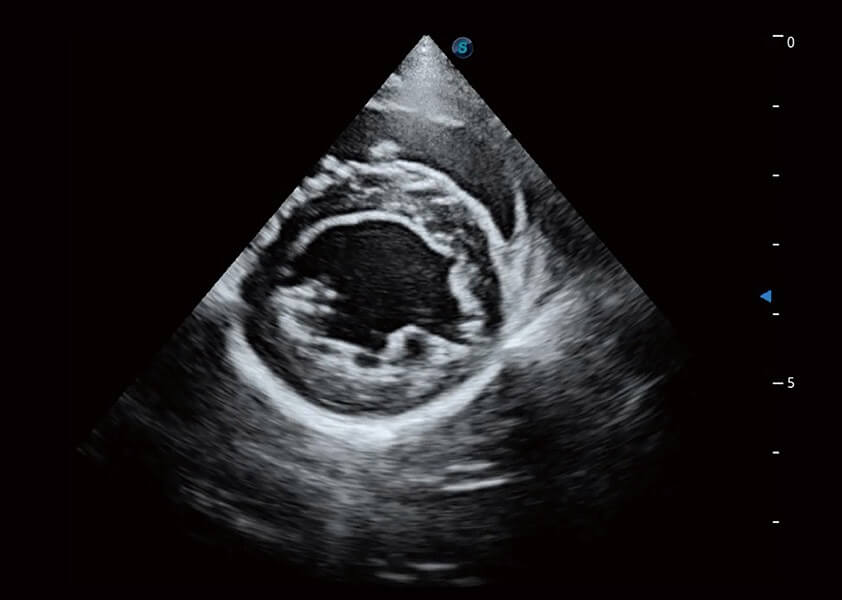

ProPet 60 作为一款高端台式动物超声设备,为动物医生的日常诊断提供了一系列贴合动物临床需求、解决临床实际问题的高级成像功能。凭借全系列高清探头,满足医生对腹部、心脏、生殖、浅表、肌骨等成像的所有需求,切实帮助您提升检查效率,提高诊断信心。

动物是人类最亲密的朋友和最值得信赖的伙伴。银河集团官网也一直致力于探索动物专用的超声影像解决方案。 全新推出的ProPet系列,是银河集团官网在动物超声影像智能化、专业化、精准化的一次跨越式革新。动物不能用言语来表述自己的不适,通过超声影像,ProPet系列搭建了动物医生与不同物种沟通的“桥梁”,为动物医生注入了“治愈之力”。